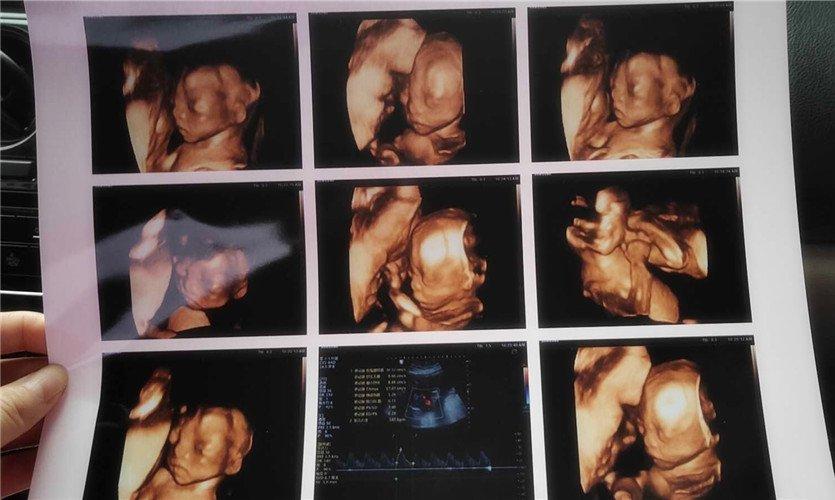

四維彩超是一種先進的醫學影像技術,通過實時觀察胎兒在母體內的活動情況,為醫生提供了豐富的診斷信息,在四維彩超下,我們可以清晰地觀察到胎兒的蛋蛋(睪丸)的形態、位置和大小等特征,胎兒蛋蛋是男性生殖系統的重要組成部分,對于胎兒的生長發育具有重要意義。

四維彩超下胎兒蛋蛋的樣子

在四維彩超下,胎兒蛋蛋呈現出特定的形態和外觀,通常情況下,胎兒蛋蛋呈現出圓形或橢圓形,表面光滑,內部回聲均勻,隨著胎兒的發育,蛋蛋會逐漸增大,并呈現出明顯的性別特征,醫生可以通過四維彩超技術,對胎兒蛋蛋的大小、形態和位置進行評估,以判斷胎兒生殖系統的健康狀況。

胎兒蛋蛋的發育是一個復雜的過程,受到多種因素的影響,在胎兒發育的早期階段,蛋蛋位于腹腔內,隨著胎兒的生長發育,蛋蛋逐漸下降至陰囊,這個過程受到激素、遺傳和環境等多種因素的影響,在四維彩超的觀測下,我們可以實時了解胎兒蛋蛋的發育過程,及時發現異常情況并采取相應的治療措施。

四維彩超技術在評估胎兒蛋蛋發育方面具有重要意義,通過四維彩超,醫生可以實時觀察胎兒蛋蛋的形態、位置和大小等特征,了解胎兒生殖系統的發育情況,四維彩超還可以幫助醫生發現可能的異常情況,如睪丸未降、睪丸囊腫等,為及時采取治療措施提供依據。